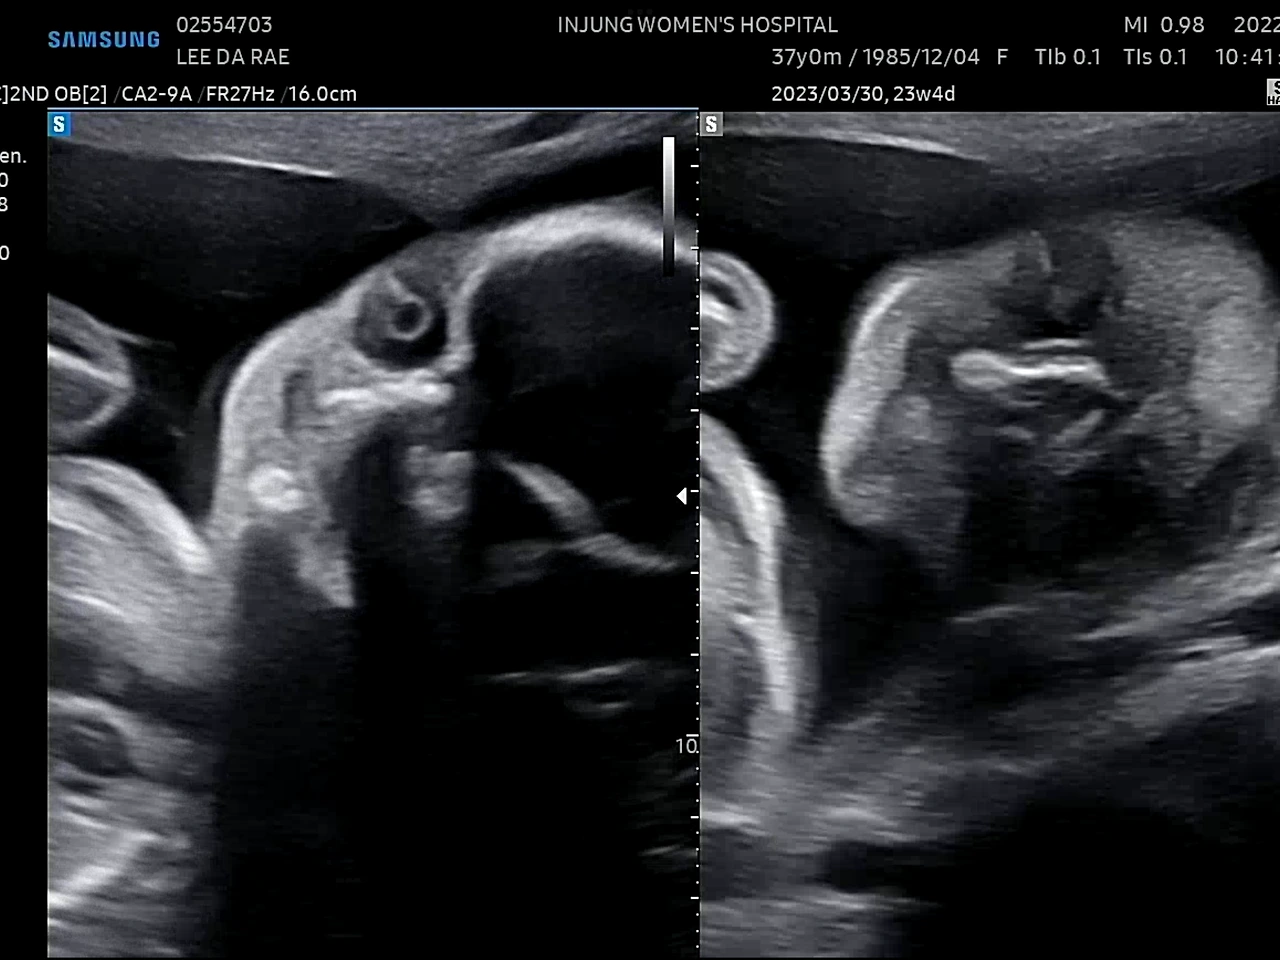

귀여운 얼굴

23주에 정밀초음파 검사를 받았다. 1차 기형아 검사에서 고위험군으로 나온 후로 모든 검사가 겁이 난다.(니프티검사에서 정상판정) 초음파 선생님(?)이 포도의 심장을 천천히 보시는데 한동안 아무 말씀도 없으시길래 너무 긴장이 됐다. 다행히 포도는 건강했다. 선생님이 아이가 쉬지 않고 움직인다고 하셨다. 아인이 때도 아이가 활발하다는 얘길 들었는데ㅋㅋ 남매라 그런가 비슷하네. 얼른 만나고 싶다 포도야!